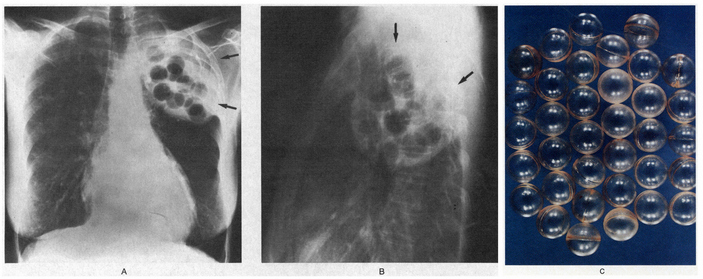

Рентгеновский снимок пациентки с пломбажем из шариков для пинг-понга. Фото из статьи N. Khan, 2014. Unusual chest radiograph finding plombs old depths

Рентгенограммы грудной клетки в задней (A) и боковой (B) проекции у 64-летней женщины. Пациентка лечилась от туберкулеза в 1953 году, ей удалили наружный листок плевры и заполнили пространство люцитовыми шариками (стрелки). Пациентка более туберкулезом не болела. На рентгеновских снимках шарики из люцита видны только благодаря их кальцификации. C — образец таких шариков, каждый приблизительно 2,5 см в диаметре (две трети размера мячика для пинг-понга), взятых посмертно у другого пациента. Фото из статьи D. J. Mond, A. Khan, 1994. Lucite-Ball Plombage